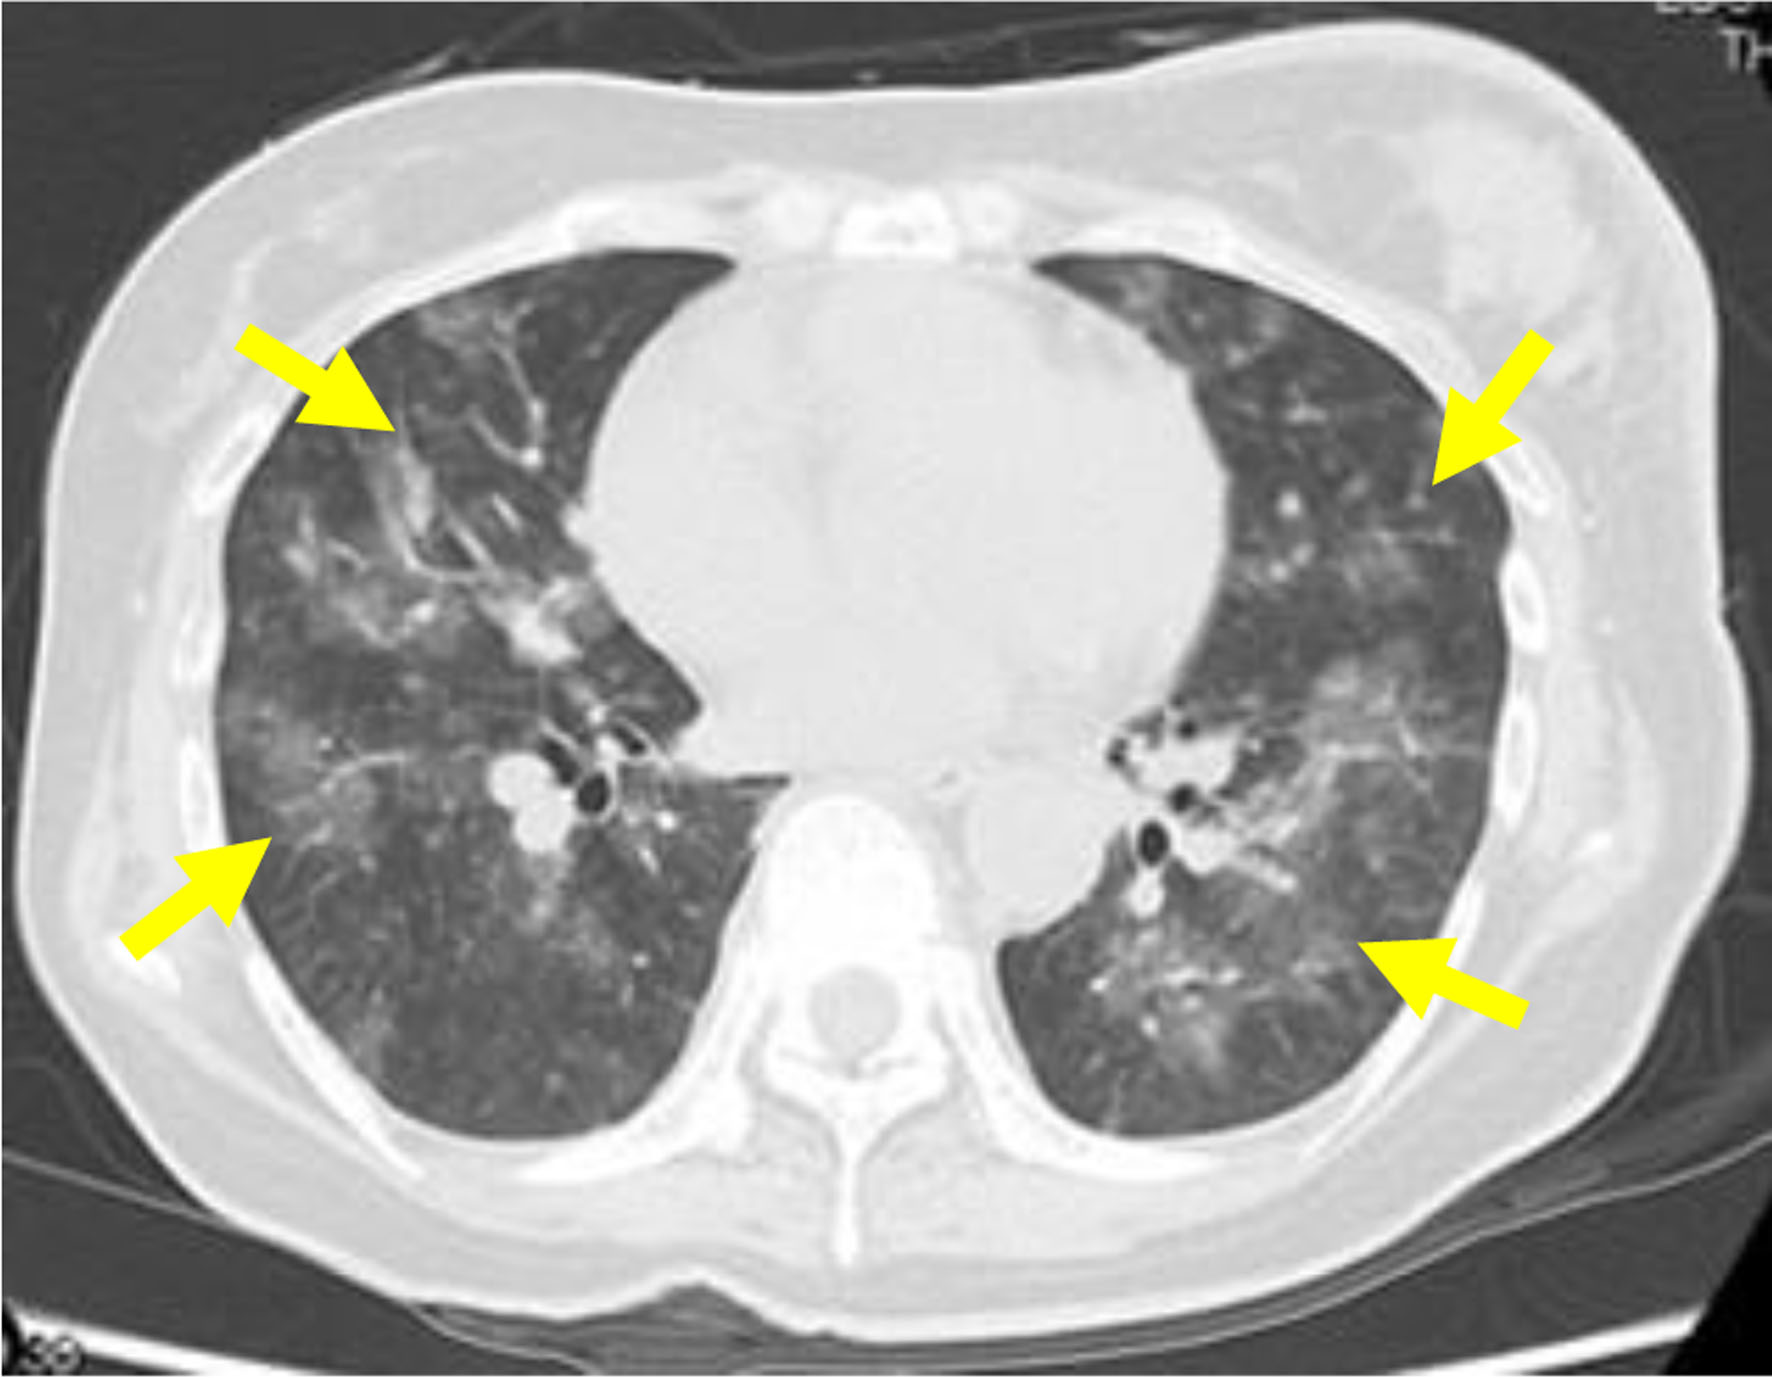

The administration of the upfront triple combination therapy for PH comprising epoprostenol, tadalafil, macitentan, and DIC management involving a continuous infusion of heparin at 10,000 U/day, thrombomodulin alpha at 380 U/kg/day, and chemotherapy for breast cancer (paclitaxel (PTX) at a dose of 90 mg/m2, every 3 weeks with a 1-week break; and bevacizumab at a dose of 10 mg/kg, every 2 weeks) were initiated immediately. Two days after the commencement of chemotherapy, the patient showed decreased oxygenation, and the CT scan taken revealed multiple infiltrations in both lungs (Fig. 3). Pulmonary hemorrhage due to reperfusion was suspected, prompting the discontinuation of the anticoagulation therapy. Six days after the initiation of chemotherapy, the patient’s oxygenation gradually improved, and the DIC resolved. Consequently, the patient was discharged from the intensive care unit 7 days after the commencement of chemotherapy. On day 10 post-chemotherapy, the patient’s mean pulmonary artery pressure decreased to 29 mm Hg, and she was eventually discharged on day 27 after initiating chemotherapy with a mean pulmonary artery pressure of 20 mm Hg.

![]() Click for large image | Figure 3. Computed tomography scan showing multiple infiltrations in both lungs (yellow arrows) 2 days after the start of chemotherapy. |